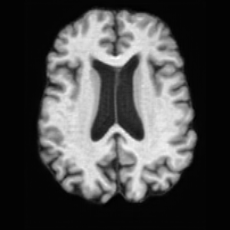

Conditional Generation. Fig. 4 (b) shows conditional generation results given a lesion mask. Conditioned on a single lesion mask, USB can generate an unlimited brain image samples that embed the specified lesion, producing diverse anatomical appearances while maintaining faithful pathological localization. As illustrated by the samples along each row, the generated pathological images exhibit variations in intensity, texture, and local tissue response.

In Tab. 1, we present the first quantitative benchmark evaluation of both generation tasks. For the unconditional generation task, we generated 256 paired lesion–brain samples for each lesion type (stroke and WMH). For the conditional generation task, we used masks from the ATLAS and ISLES test sets as stroke lesions, and masks from the ADNI test set as WMH lesions. Notably, for each lesion type, the unconditional generation achieved superior quantitative performance, highlighting that the paired diffusion mechanism effectively generates coherent lesion-brain pairs through joint modeling between USBbrain and USBlesion. Additional generation results are provided in Suppl. A.